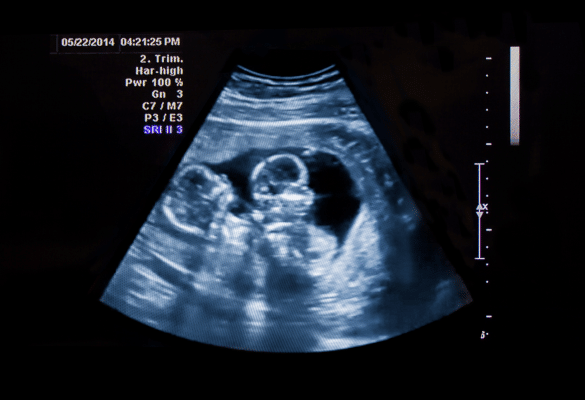

Apprendre qu’on attend des jumeaux, c’est une double dose de bonheur… et une double dose de suivi ! Les grossesses gémellaires nécessitent une surveillance plus étroite : elles sont associées à un risque plus élevé de prématurité, d’hypertension et de césarienne.

Les grossesses de triplés, elles, restent extrêmement rares et font l’objet d’un suivi médical très encadré. Or, selon la Haute Autorité de Santé (HAS), ces situations nécessitent un accompagnement renforcé pour protéger la santé de la mère et des bébés.

En France, les équipes médicales assurent aujourd’hui un suivi attentif des grossesses gémellaires, et la plupart se déroulent sans incident. Votre équipe vous chouchoute simplement un peu plus jusqu’à l’accouchement.